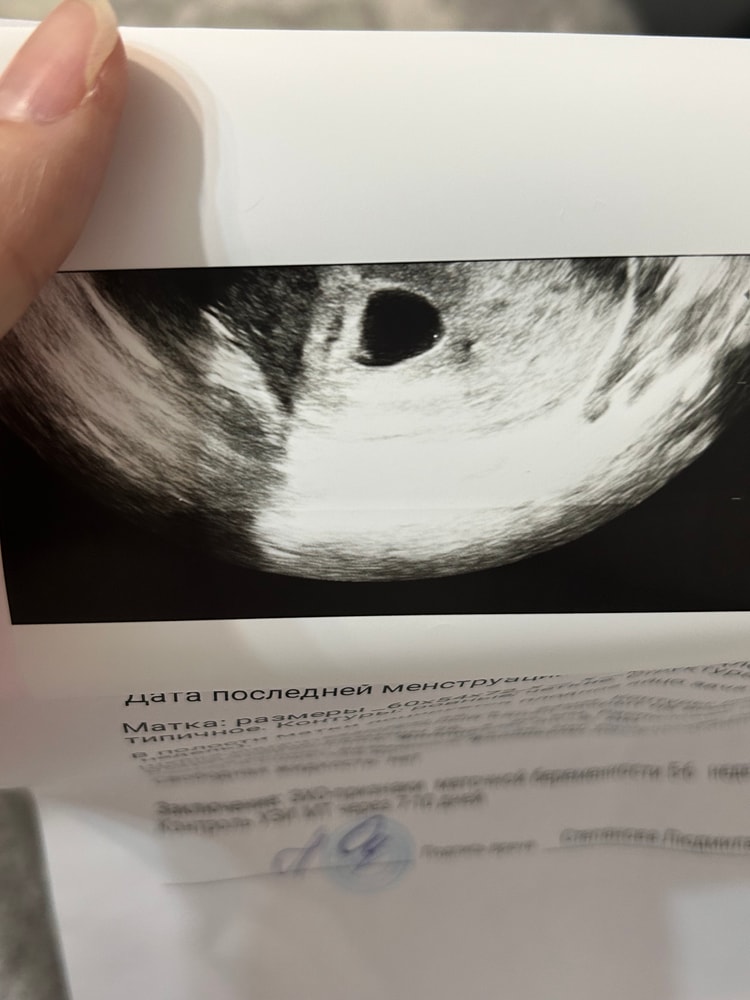

Срок 5 недель 4 дня. На узи сказали, что эмбрион слишком маленький для 5 недель, но в заключении записали срок 5-6 недель. Не знаю что думать, нормально ли или стоит переживать, след раз пойду только 19